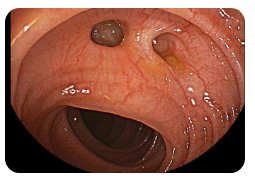

💩 왼쪽 옆구리 통증 설사

설사와 함께 왼쪽 옆구리 통증이 발생한다면 대장과 관련된 질환을 고려해볼 수 있습니다. 과민성 대장 증후군, 게실염, 크론병 등이 주요 원인입니다. 이들 질환은 장내 염증이나 긴장으로 인해 왼쪽 하복부 및 옆구리에 통증을 유발합니다. 스트레스나 식습관에 따라 증상이 심해지며, 설사와 변비가 번갈아 나타나기도 합니다. 장기간 증상이 지속되면 대장 내시경 검사를 통해 정확한 진단이 필요합니다.